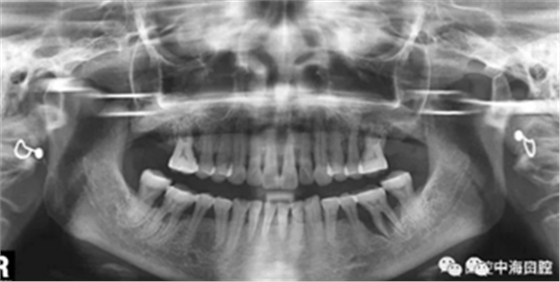

下面這兩張圖,據(jù)說拔牙費(fèi)時1.5小時,收費(fèi)14000元。